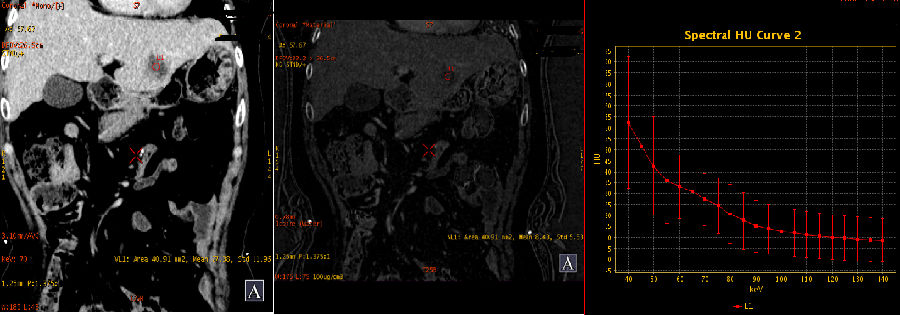

3、延迟期能谱分析

左侧病灶CT值及碘含量持续升高

肝右叶两个病灶能谱曲线仍然接近一致